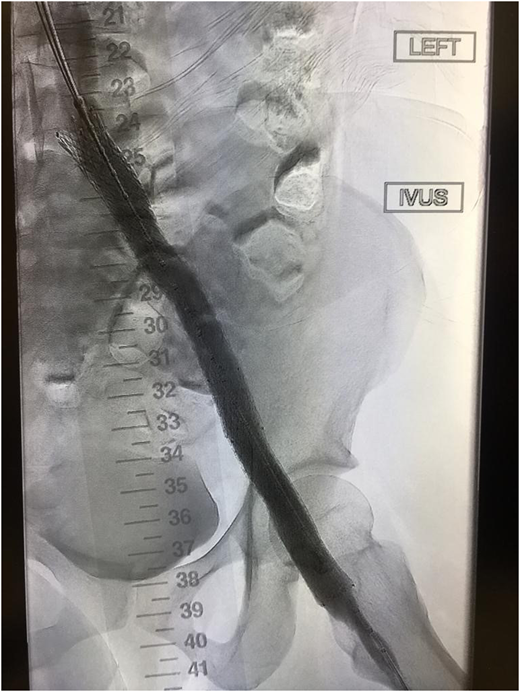

Improved vascular flow after venous stenting using the Abre stent (Medtronic).